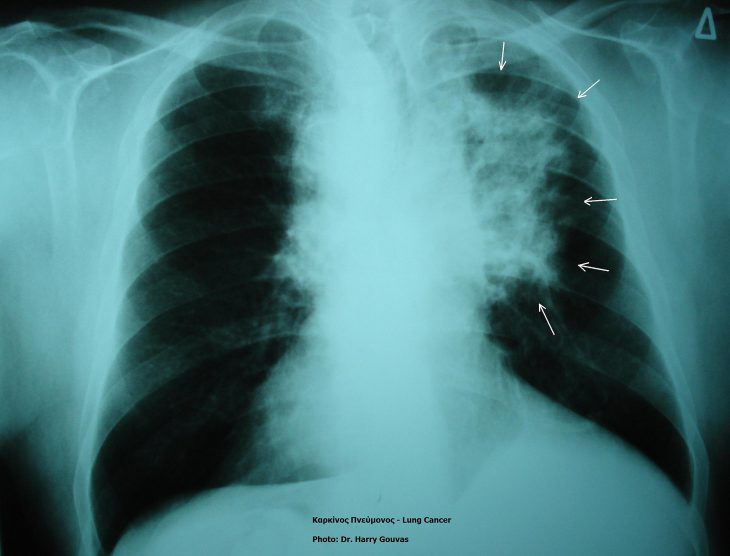

Researchers are looking for techniques that can predict how well a tumor will respond to a treatment. One way to do this is by measuring “biomarkers.” Biomarkers for cancer are “signals” that a tumor has a certain trait that might make it susceptible to a medication or procedure. Non-small cell lung cancer is the most common type of lung cancer found.